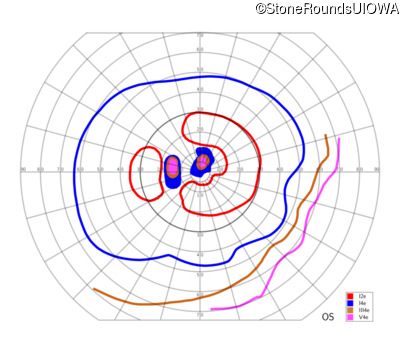

This 59 year old woman first noticed a reduction in her visual acuity and photophobia in her late teens.

| AD Cone and Cone Rod Dystrophy | GUCA1A | Glu155Gly GAG>GGG | AD |

Glu155Gly GAG>GGG